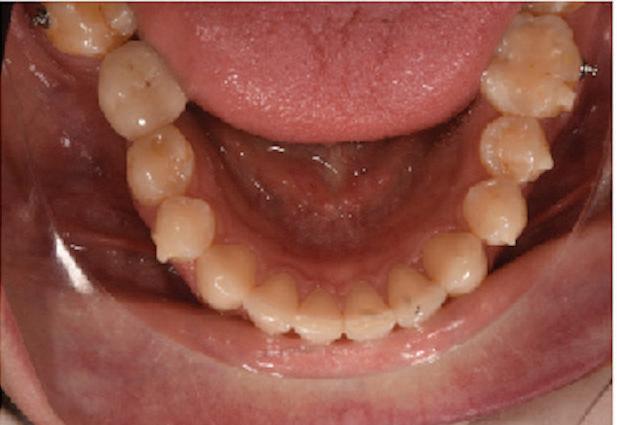

Пациентът постъпи в моята клини ка с наличие на темпоромандибуларен дисфункционален болков синдром, едно странно изместен диск с редукция в дяс ната става, клас II, подклас 2, тесни гор на и долна челюст със струпване, дъл бок овърбайт

орални снимки и снимки на позата, пал пация на мускулите, брукс-чекър, оклу зограми, кондилография, рентгеногра фии, СВСТ и ядрено-магнитен резонанс на темпоромандибуларните стави). Преди началото на ортодонтското лечение всички стари възстановява ния бяха свалени и бяха заменени с дъл госрочни временни от хибридна керами ка. На девитализираните зъби бе прове дено ендодонтско релечение. Индивиду ализиран оклузален сплинт бе направен с цел да се постигне контролирано репо зициониране на долната челюст, като носенето му продължи три месеца до възстановяване на правилната позиция на ставния диск и затихване на орофаци алната болка и дискомфорт в ставата. Брекетите в горната челюст бяха за лепени, за да започне подреждането и нивелирането на зъбите, докато паци ентът все още носеше сплинта. След края на терапията със сплинта бе на правена кондилография, за да се потвър ди триизмерната позиция на долната челюст. След залепване на брекетите в долна

тация на долната челюст. Дъга GUMMETAL с tip-back извивки бе поставена в долната челюст за ниве лиране кривата на Шпее. Случаят бе финализиран с 19x25 SS дъги в горната и долната зъбна дъга за координиране. Преди да се изготви финалният восъ чен моделаж, естетичните и лицеви те характеристики бяха анализирани с помощта на дигитален дизайн на ус мивката, за да се създаде мок-ъп, чии то форма и размери да бъдат одобрени от пациента. Бе оценена фонетиката и бяха заснети лицеви снимки и видеа. Зъ бите бяха изпилени, като препарация та бе изцяло водена от функционалния восъчен моделаж, прехвърлен в устата на пациента. След препарацията восъч ният моделаж бе напаснат и насложен върху препарационния модел и бе фрезо ван от e-max multi bl 1. Циментирането на финалните конструкции бе направе но при изолация с кофердам, следвайки адхезивния протокол. След циментирането бе направено проследяване на оклузията чрез снема не на отпечатъци, монтиране на моде лите в артикулатор в окончателната интеркуспидация и внимателно прове ряване за наличие на блокажи при воде ни движения.

та челюст 4 минивинта (TADs) бяха по ставени в максилата – 2 в небцето и 2 интрарадикуларно във фронта, с цел да се извърши интрузия на цялата зъбна дъга, да се коригира гингивалната усмивка и да се позволи провеждането на обратна на часовниковата стрелка авторо